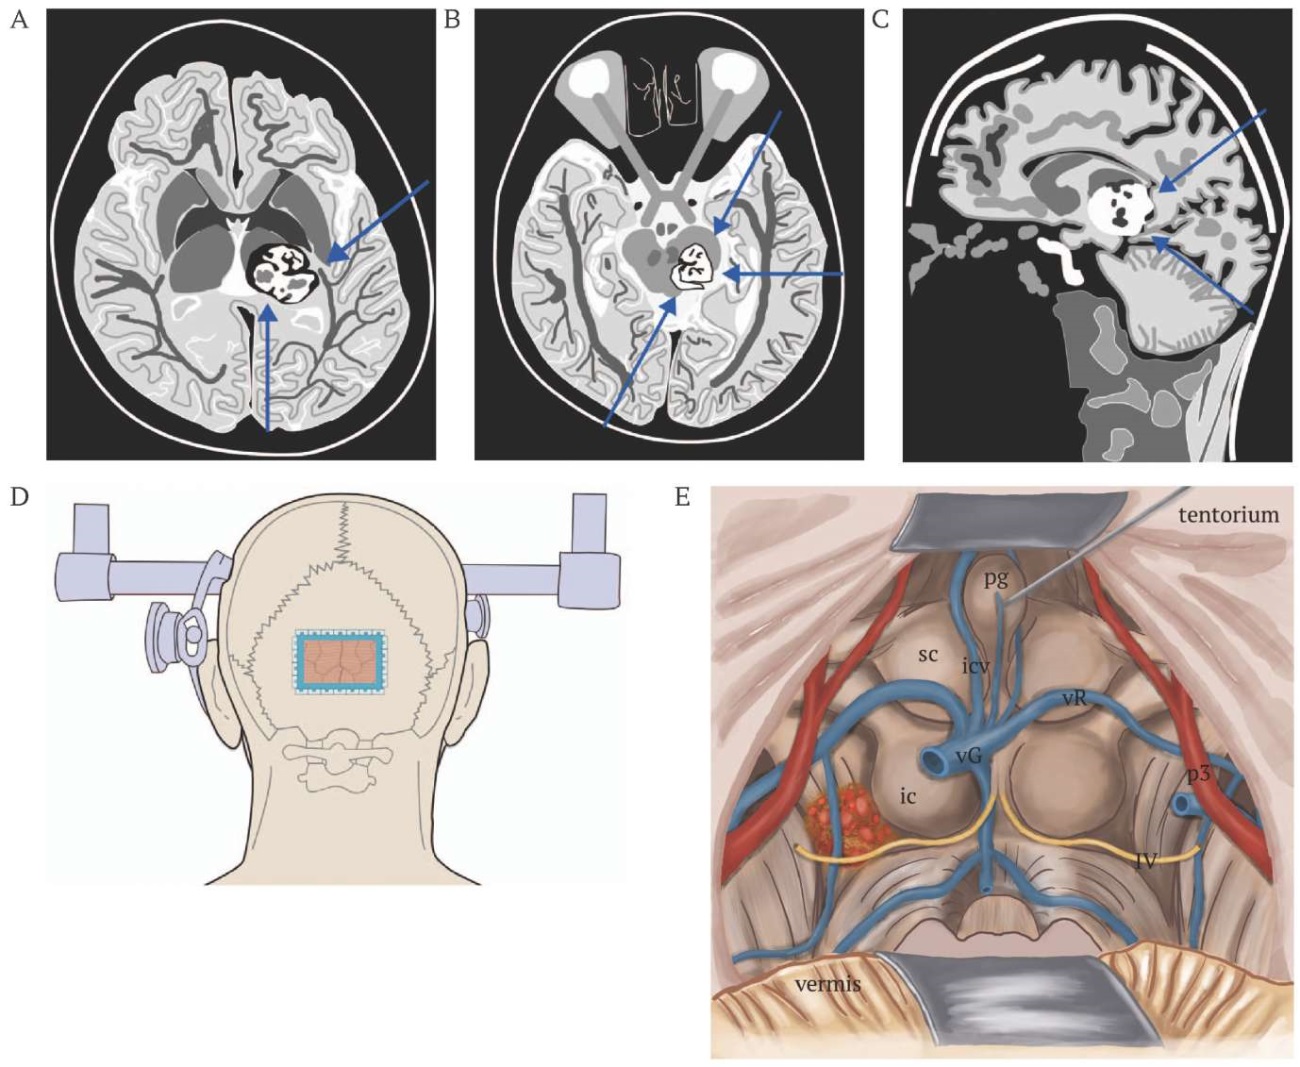

С целью предотвратить послеоперационный неврологический дефицит, оцененный по дополнительным шкалам (4 балла по Spetzler–Martin [11] и 3 балла по Lawton–Young [12]), для радикальной резекции каверномы выбрана медианная субокципитальная краниотомия и контралатеральный супрацеребеллярный инфратенториальный доступ с последующей резекцией каверномы (рис. 2A–E).

РИС. 2. Схематическое изображение локализации каверномы дорсальной поверхности среднего мозга и выбора стратегии ее резекции.

А. Аксиальный срез. Стрелками показаны доступы к среднему мозгу: левая нижняя – супрацеребеллярный инфратенториальный; правая верхняя – задний субтемпоральный.

В. Аксиальный срез. Стрелками показаны доступы к среднему мозгу: левая нижняя – контралатеральный супрацеребеллярный инфратенториальный; правая верхняя – передний субтемпоральный; правая нижняя – задний субтемпоральный доступы.

С. Сагиттальный срез. Стрелками показаны доступы к среднему мозгу: правая верхняя – затылочный транстенториальный; правая нижняя – супрацеребеллярный инфратенториальный.

D. Обнажение каверномы с помощью торкулярной краниотомии и супрацеребеллярного инфратенториального доступа (голубая линия).

Е. Доступ к каверноме через супрацеребеллярную инфратенториальную плоскость и четверохолмную цистерну; идентификация восходящих глубоких вен мозга; определение питающих артерий моста и среднего мозга; обзор боковых отделов; диссекция четверохолмной цистерны для обеспечения свободного коридора (верхний вид среднего мозга, моста, тенториума с пинеальной области и верхней ножки мозжечка); мобилизация сосудов, вен, впадающих в верхний сагиттальный синус.

Примечание: ic – inferior colliculus, нижнее двухолмие; icv – internal cerebral vein, внутренняя мозговая вена; pg – pineal gland, шишковидная железа; p3 – posterior cerebral artery (segment p3), задняя мозговая артерия (сегмент р3); sc – superior colliculus, верхнее двухолмие; vG – vein of Galen, вена Галена; vR – vein of Rosenthal, вена Розенталя; IV – cranial nerves (IV pair), черепно-мозговые нервы (IV пара).